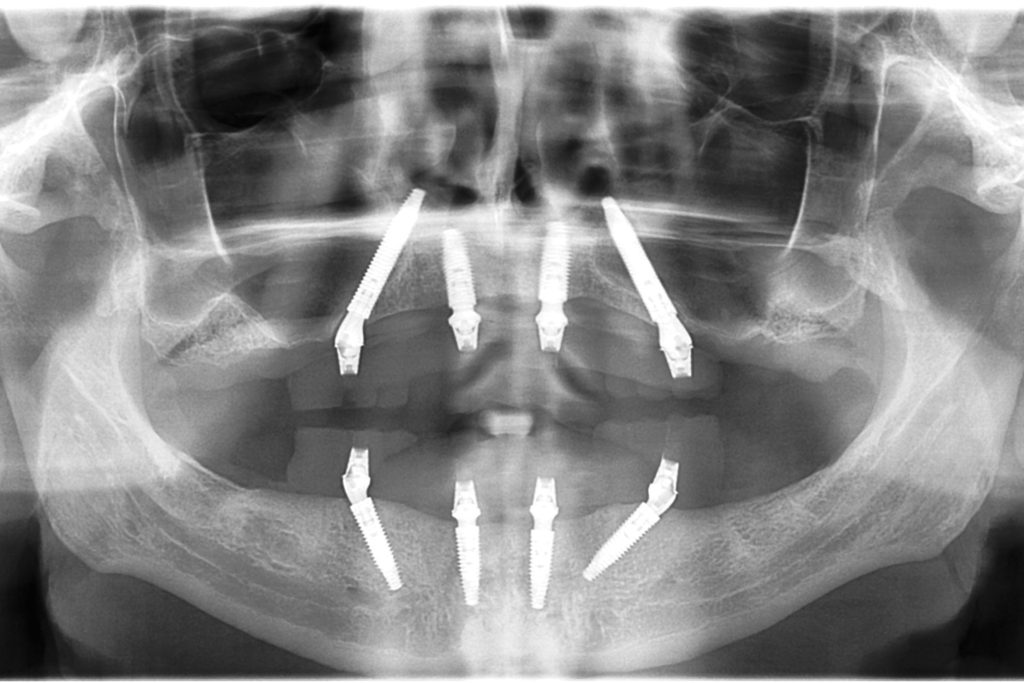

CBCT Maxilla

3D Cone Beam Computer Tomography is used for diagnostics and treatment planning